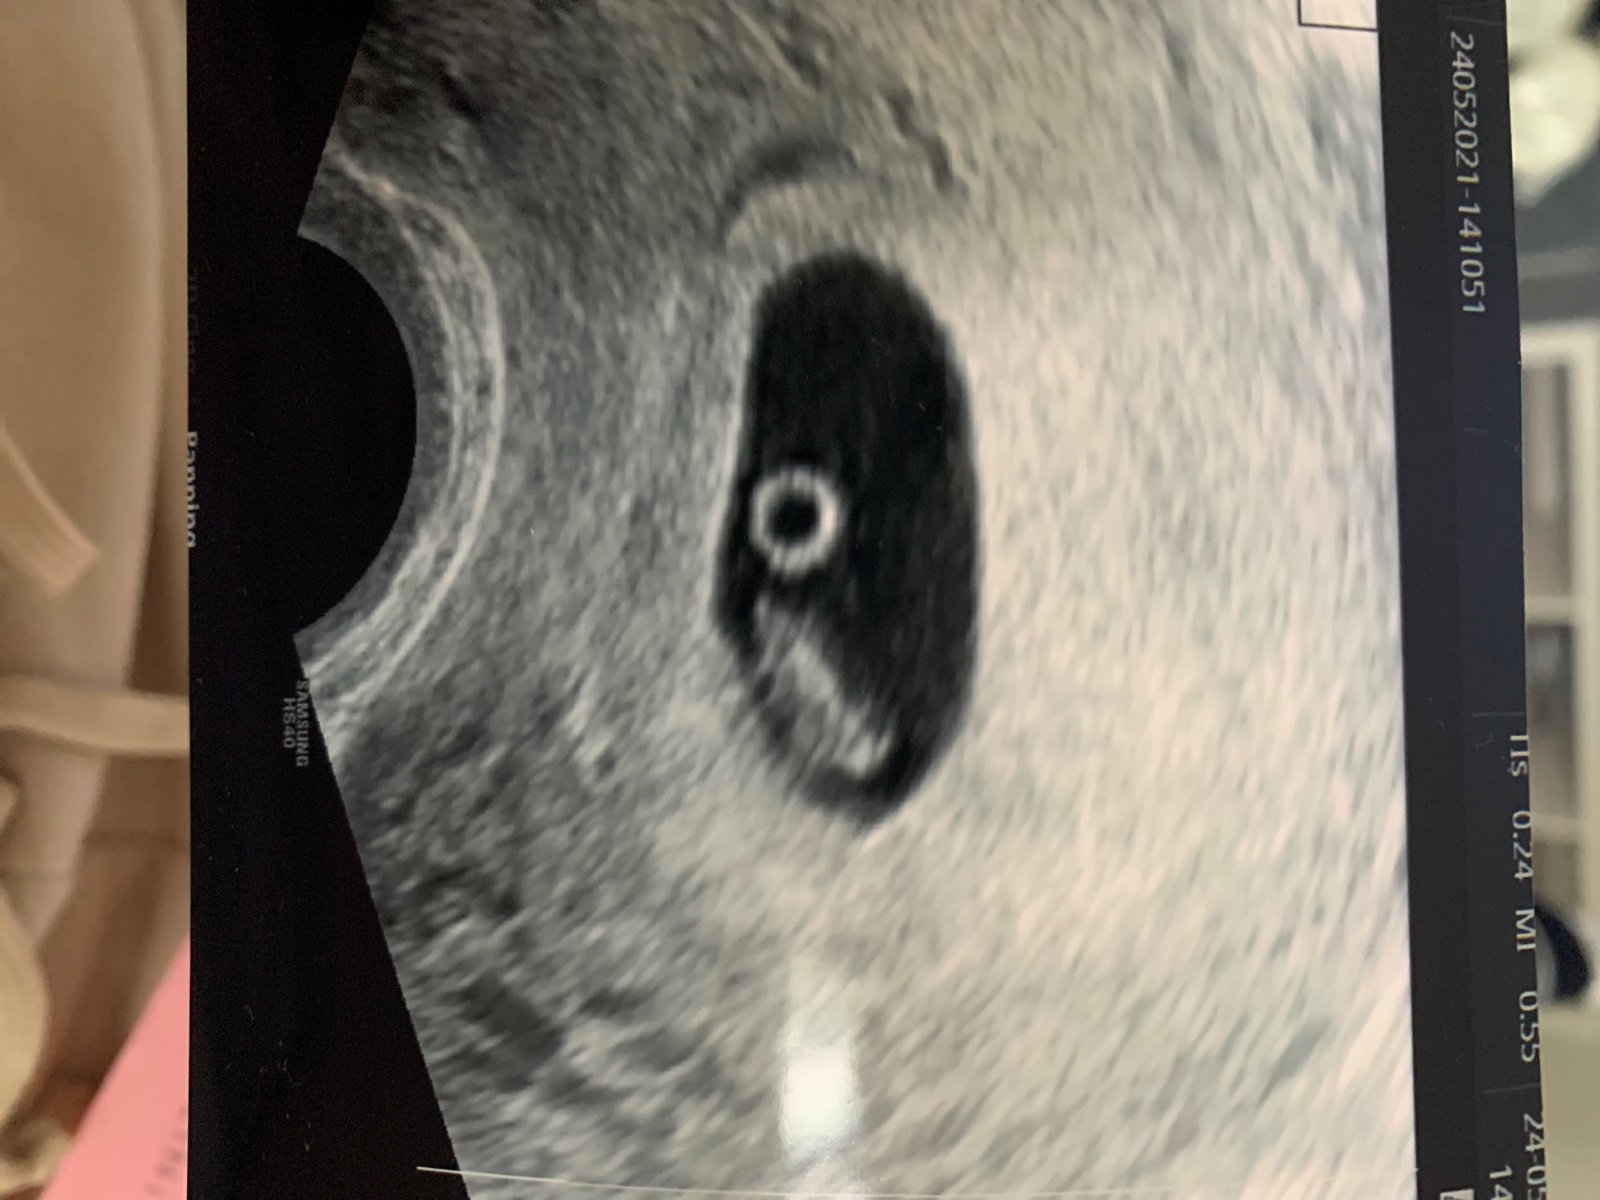

Co to je na ultrazvuku?

@flowerstone Já myslím, ze žluté tělísko z kterého je embryo vyživované a zaniká se vznikem placenty...taky jsem ho mela takhle hezky vidět